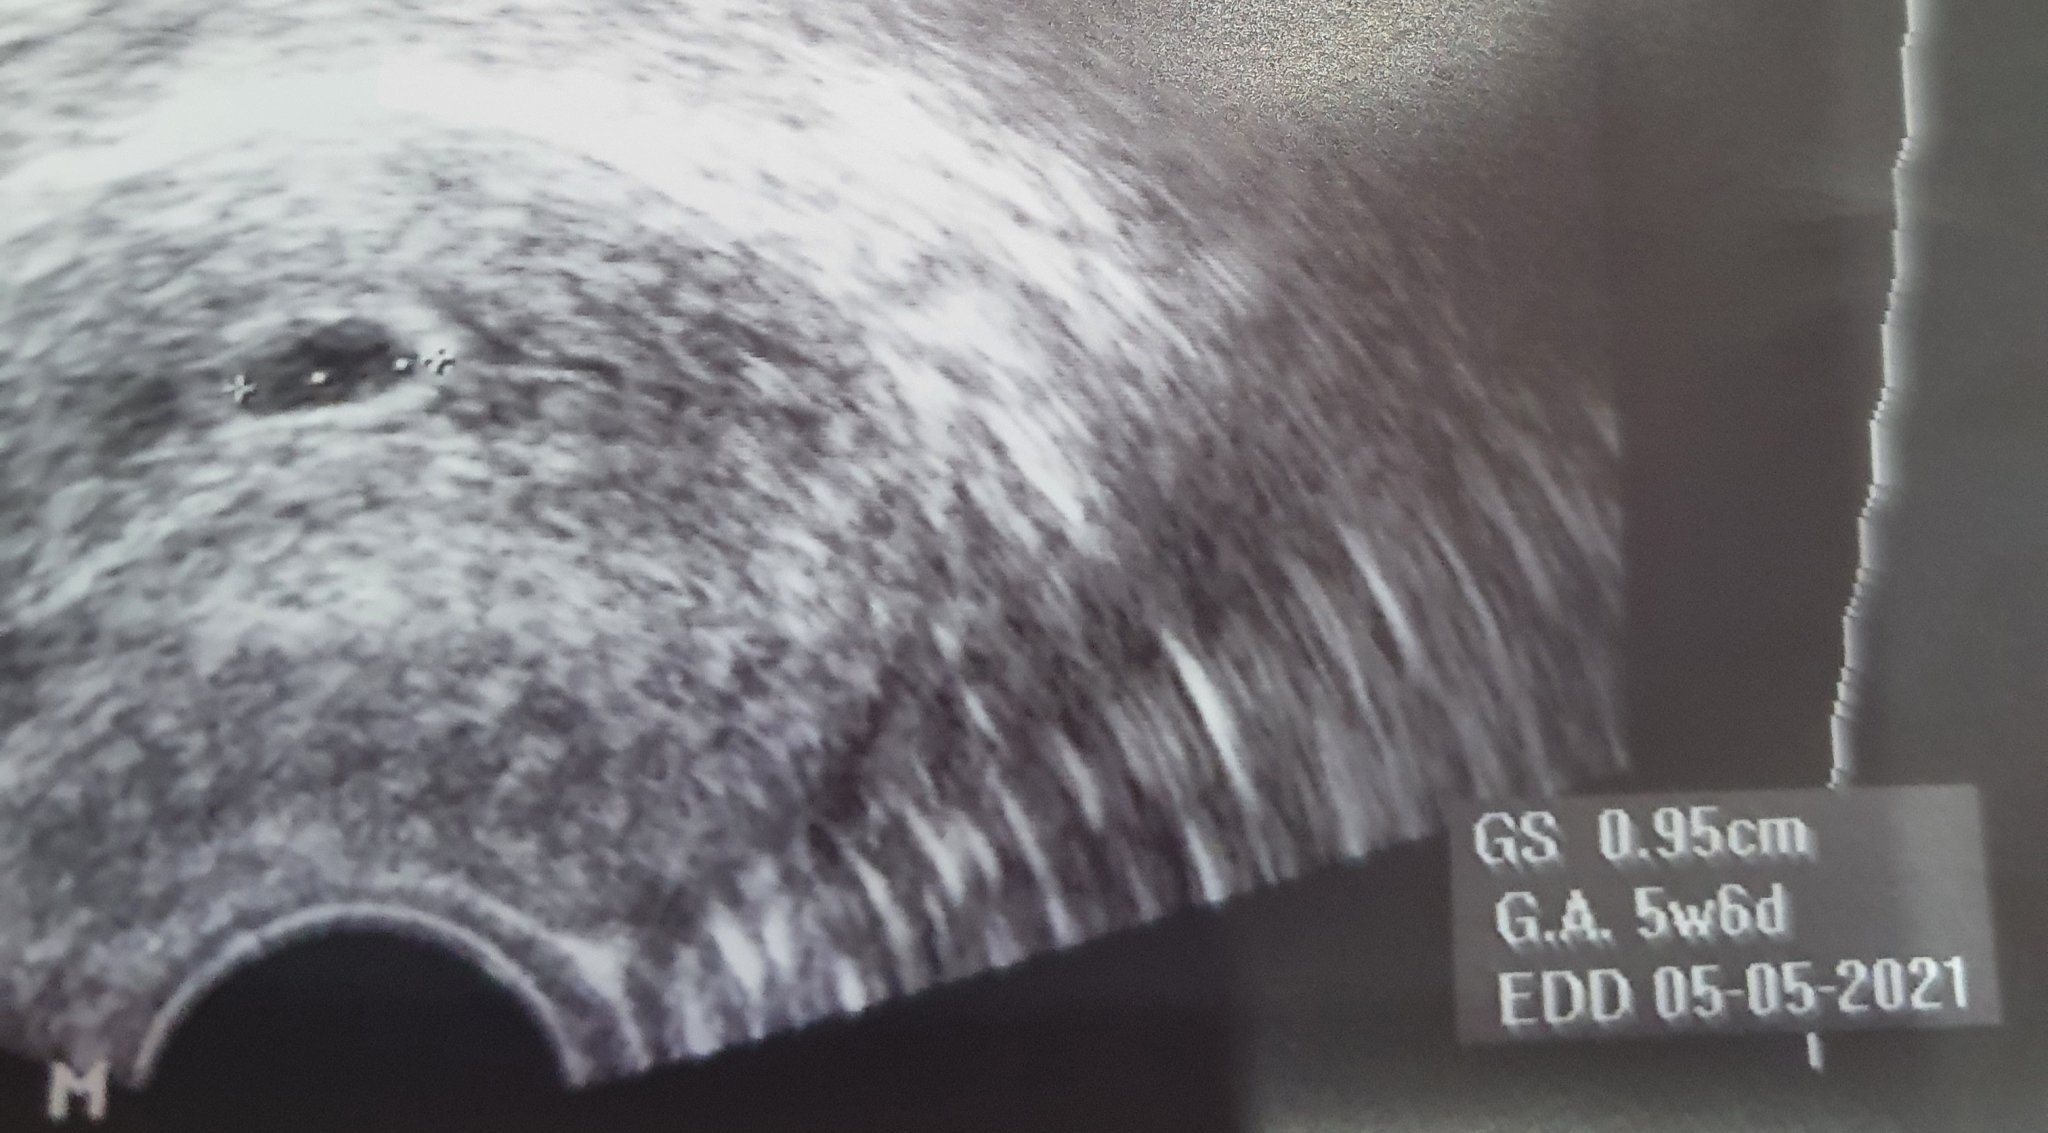

Ох дано имаме късмет Sad виж моите снимки от 2 седмици разлика в преглените

Не мога да се примиря че нещо не е наред Sad Sad

И аз така се бях притеснила, защото в 5+3 седмица при мен всичко си отговаряше, а след 1 седмица сакчето беше нарастнало само с 3мм и дори не се виждаше ембрион.